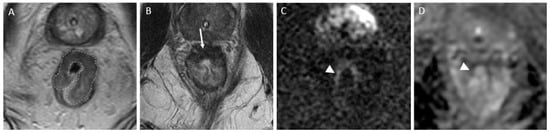

4.4.4. Mucinous Rectal Cancer